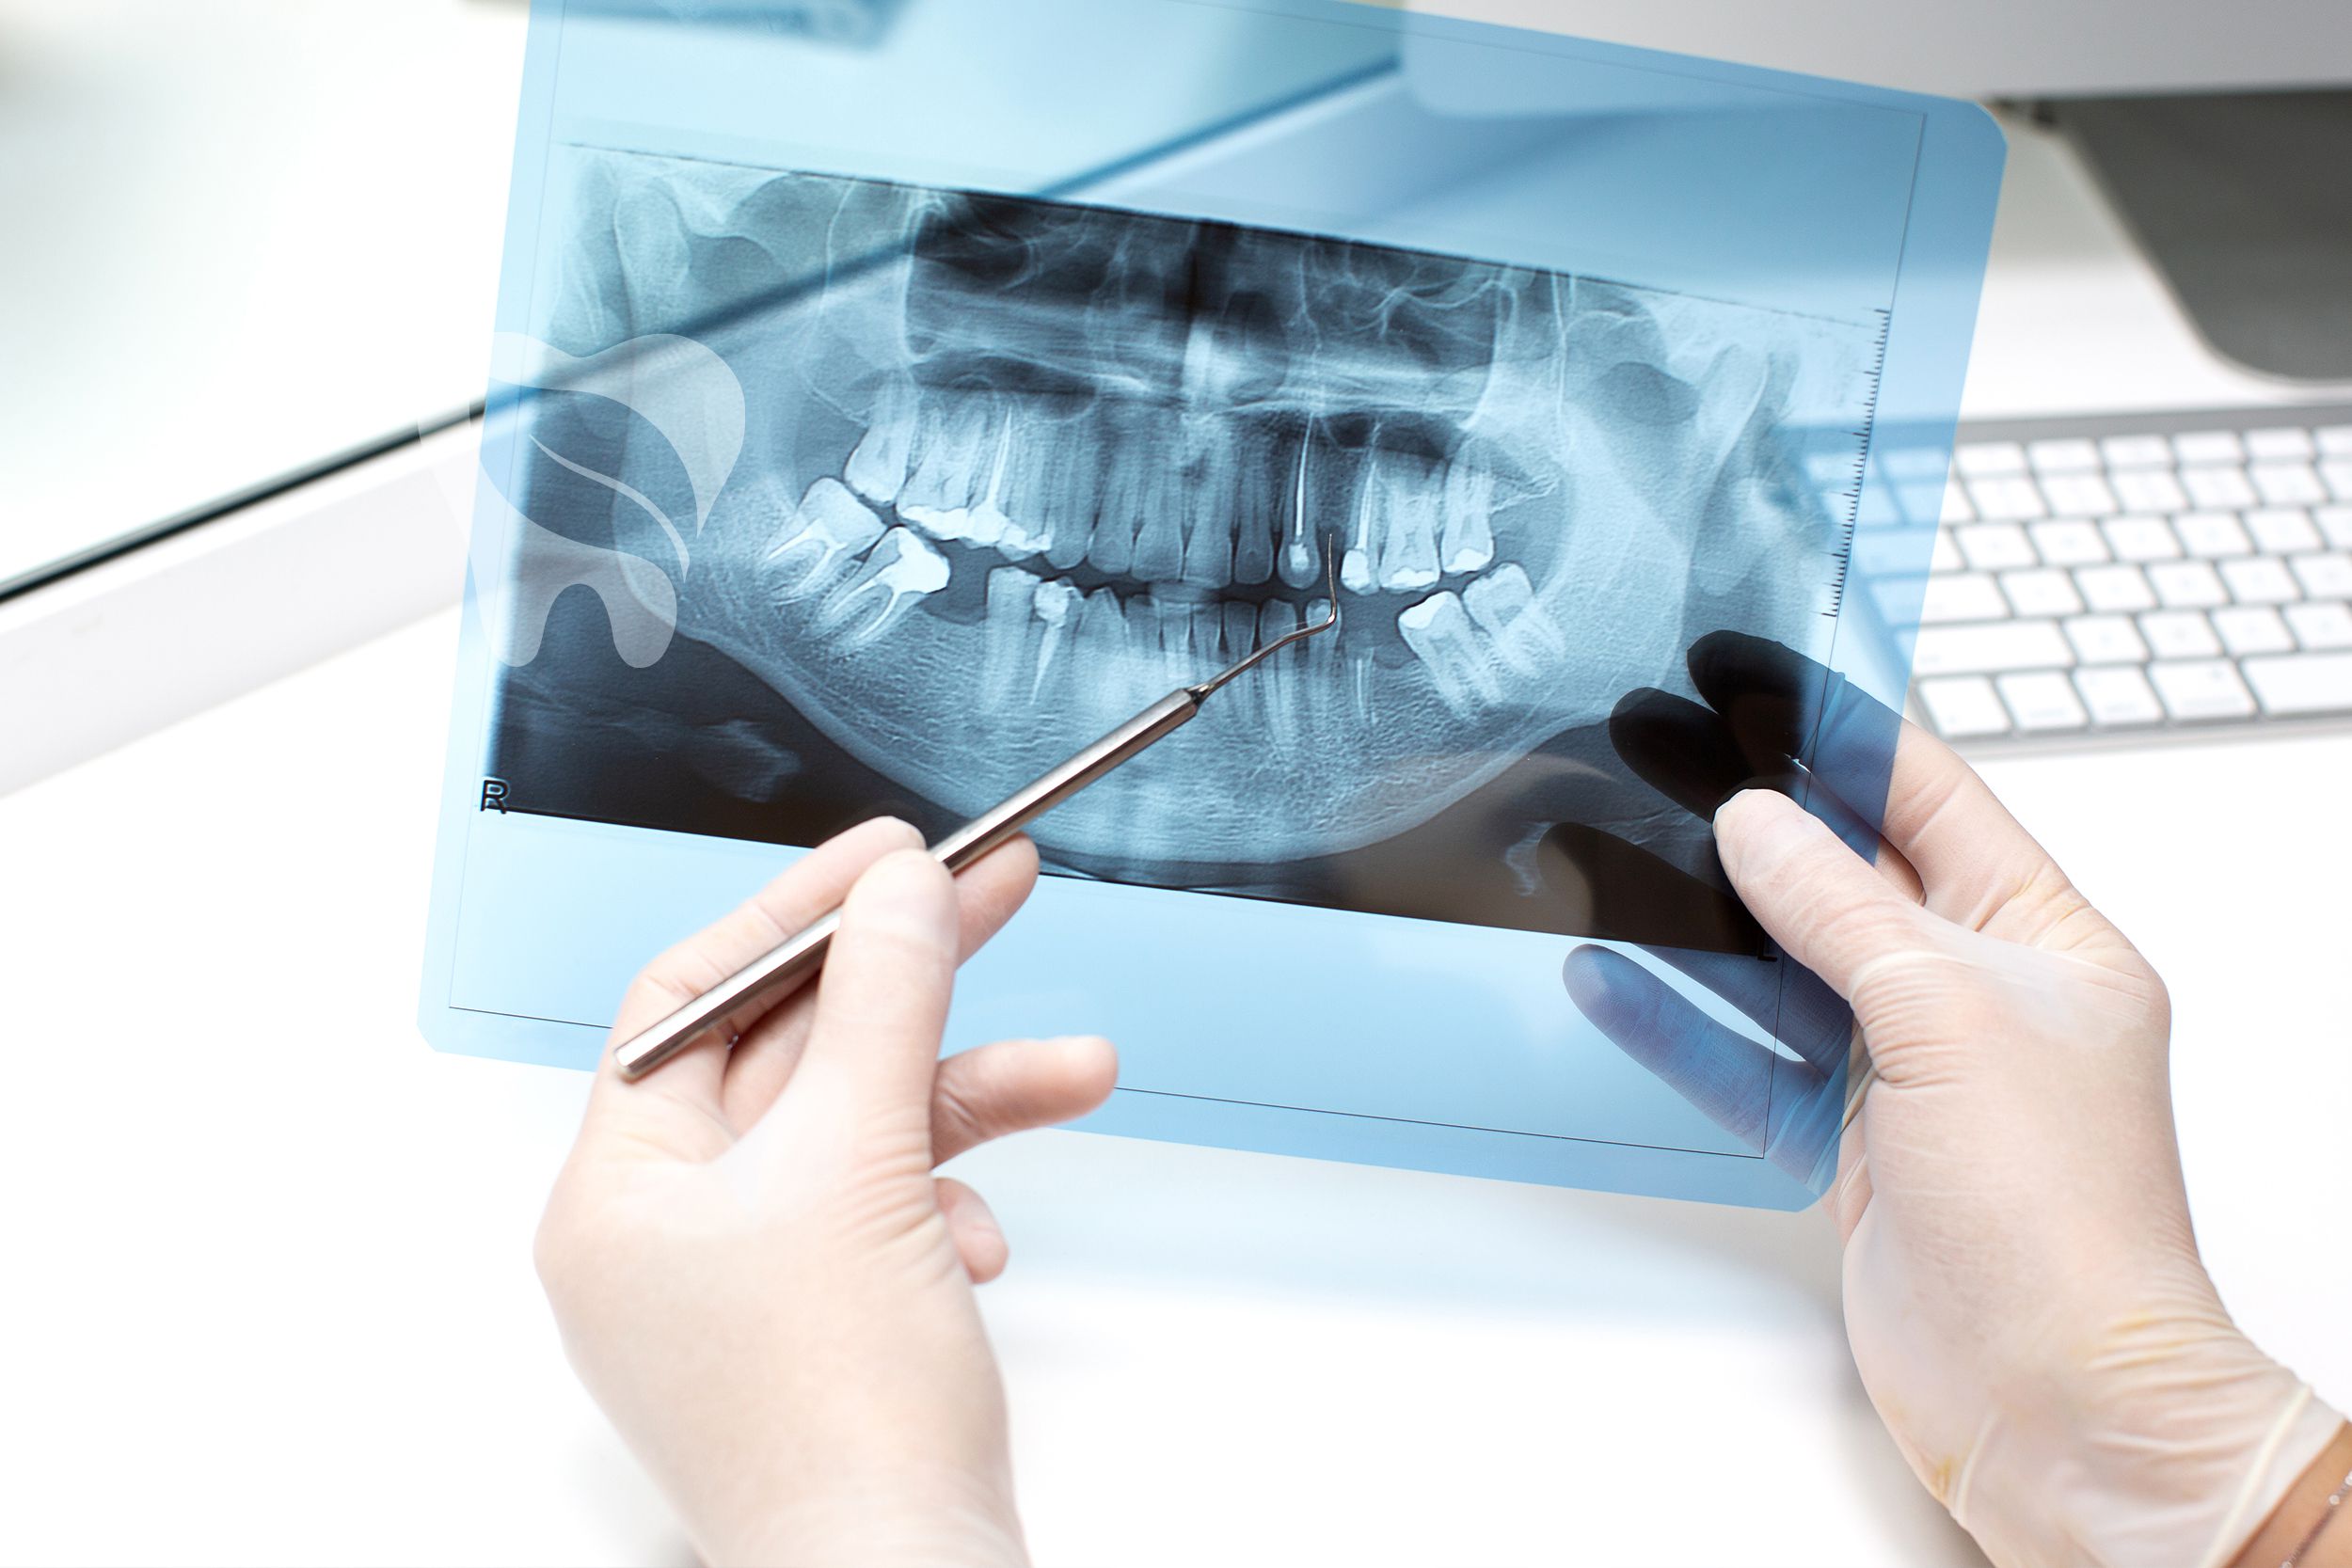

Radiology

We reinforce diagnosis with two- and three-dimensional imaging, collaborating with other departments to reach the most accurate conclusions.